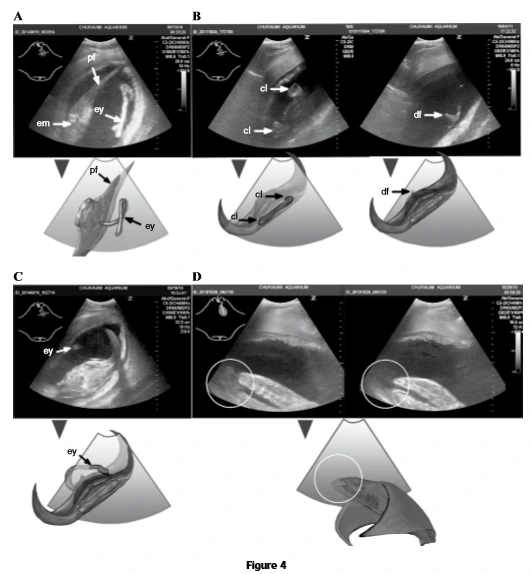

일반적으로 임산부의 뱃속을 볼 때와 유사하게 초음파장비를 사용하는 게 특징적이다.

초음파장비를 통해 살아있는 만타가오리에게 접근하여 시기별로 발달상태를 확인하였다.

초음파를 통해 관찰한 자궁 내 아기 쥐가오리